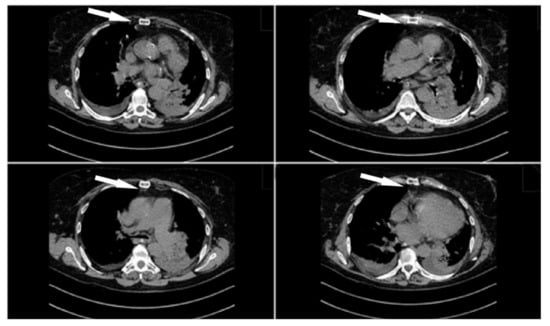

2. Case Presentation